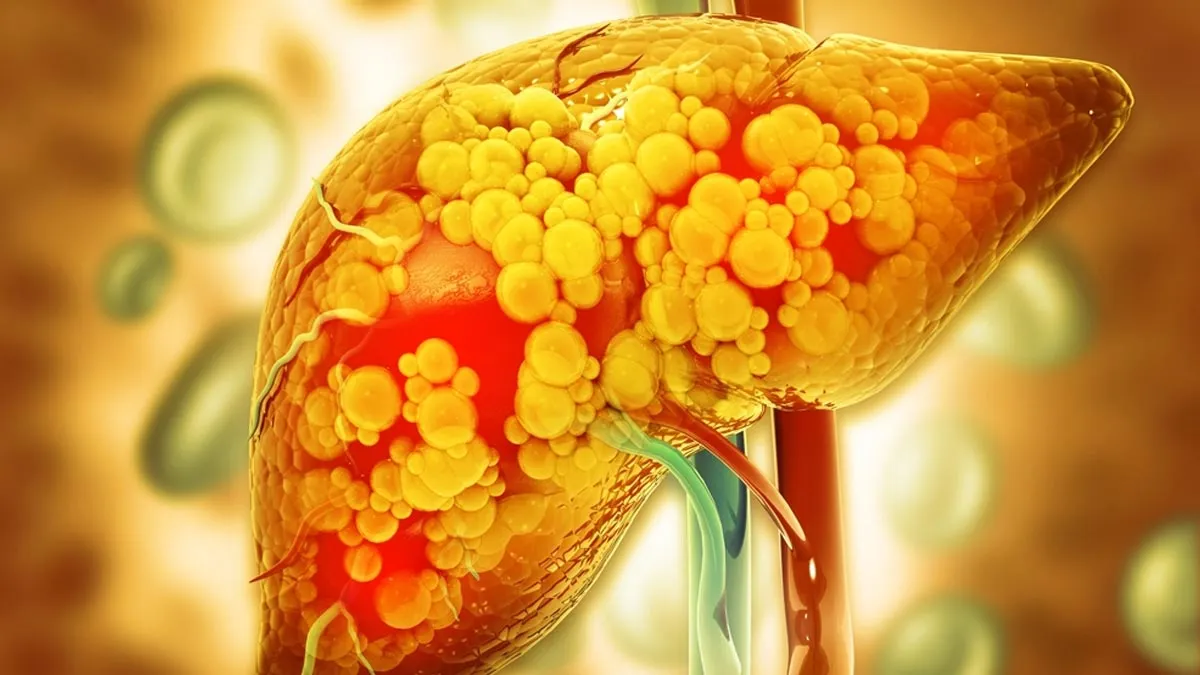

अगर आपके भी यही सवाल हैं, तो सबसे पहले तो आपको घबराने की जरूरत नहीं है। फैटी लिवर बेशक एक ऐसी कंडीशन है, जिस पर ध्यान दिया जाना जरूरी है। लेकिन, इसका मतलब यह बिल्कुल नहीं है कि इसे रिवर्स नहीं किया जा सकता है। सही खान-पान और हेल्दी लाइफस्टाइल के साथ आप फैटी लिवर को आसानी से रिवर्स कर सकती हैं। फैटी लिवर में थकान, पेट में दर्द, भूख न लगना, वजन कम होना, भूरे रंग का यूरिन आना, त्वचा में खुजली और पीलिया जैसे लक्षण नजर आते हैं। अगर आप अपने डेली रूटीन में एक्सपर्ट की बताई 10 चीजों को सही समय पर और सही तरीके से शामिल करेंगी, तो इससे फैटी लिवर के लक्षण कम होंगे और वजन भी कम करने में मदद मिलेगी। इस बारे में डाइटिशियन मनप्रीत जानकारी दे रही हैं। उन्होंने दिल्ली यूनिवर्सिटी से न्यूट्रिशन्स में मास्टर्स किया है। वह हार्मोन और गट हेल्थ कोच हैं।

फैटी लिवर के लक्षणों को रिवर्स करने के लिए एक्सपर्ट की बताई इन चीजों को डाइट का हिस्सा बनाएं। अगर आपको स्वास्थ्य से जुड़ी कोई समस्या है, तो हमें आर्टिकल के ऊपर दिए गए कमेंट बॉक्स में बताएं। हम अपने आर्टिकल्स के जरिए आपकी समस्या को हल करने की कोशिश करेंगे।